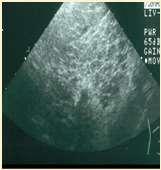

Superficialnecrolyticdermatitis

•Pathogenesis–hypoaminoacidemia(liverdisease,highlevelsof glucagoncatabolizingproteins);decreasedlevelsofzincand EFAs

•Lowlevelsofaminoacidsresultsinskinnecrosis(vacuolar degenerationofepidermalcells)

•Diagnosis

•Lowlevelsofserumaminoacids Elevatedserumglucagon

•Abdominalultrasound(“swisscheeseliver”)

•Skinbiopsies–parakeratosis,vacuolardegeneration,basalcell hyperplasia